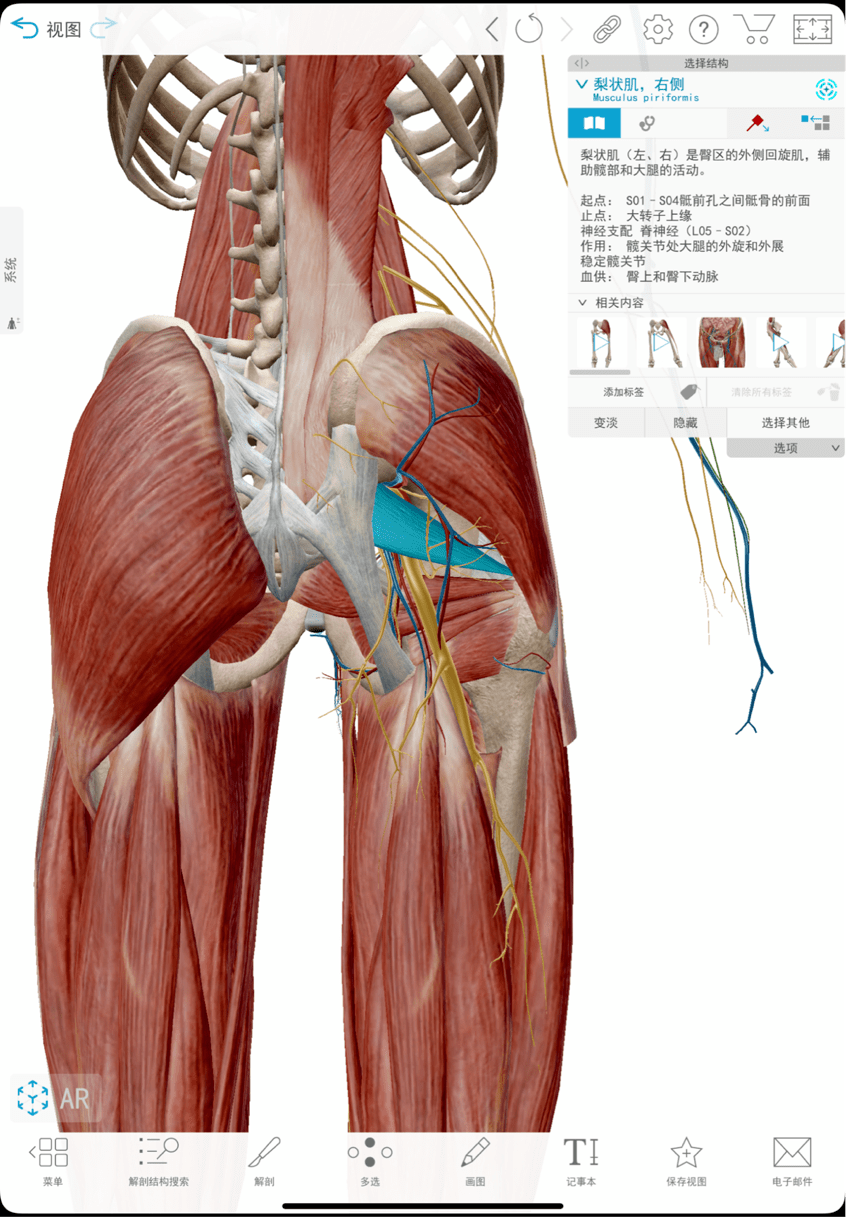

梨状肌属于臀部深层肌肉下方穿梭着坐骨神经当肌肉紧张缩短会压迫到

图片尺寸1080x1440

梨状肌是深层臀肌,而坐骨神经刚好在下方经过.

图片尺寸1080x686